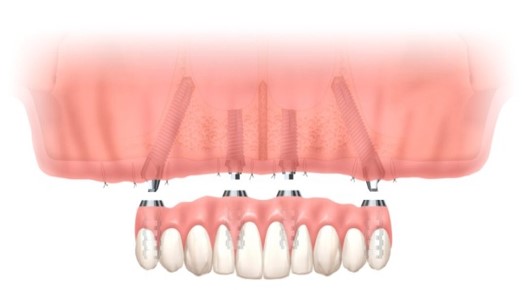

オールオン4(All-on-4®)

すべて、またはほとんどの歯を失った患者さんに適した治療法として、オールオン4(All-on-4®)があります。従来のインプラントでは上顎と下顎それぞれに8~14本のインプラントを埋め込む必要がありましたが、オールオン4では上顎と下顎に4本ずつのインプラントのみで、12本の人工歯を安定させることができます。骨量が少ない場合でも骨移植を行わずに残っている骨を活用でき、骨の状態に左右されにくいのが特徴です。ただし、高度な技術が必要なため、施術可能な歯科医師や歯科医院は限られています。